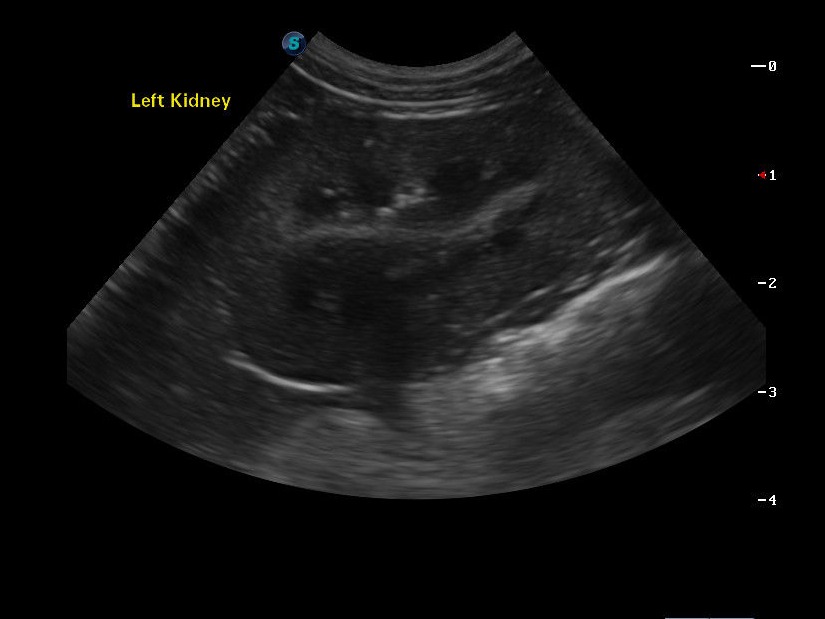

Ultrasound

Abdominal Ultrasound of a Kidney